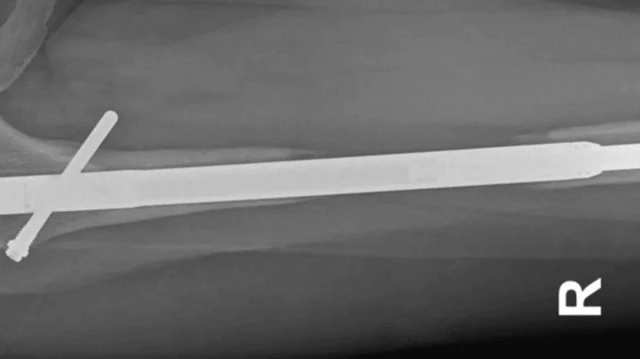

Kwa operesheni hii, maumivu fulani yanatarajiwa. Ni operesheni ambayo mifupa ya mguu imevunjwa mara mbili na fimbo ya chuma imewekwa ndani.

Fimbo za chuma huongezwa urefu hatua kwa hatua ili kuongeza urefu wa mguu na kutengenisha nusu mbili za mfupa. Mifupa iliyokatwa hupona hatua kwa hatua, ili kujaza pengo la kati.

Elaine alikwenda kufanyiwa uchunguzi, ambao ulithibitisha hofu yake. Msumari wa mguu wake wa kushoto ulikuwa umekatika kwenye fupa la paja. Alifadhaika, lakini anasema aliambiwa asiwe na wasiwasi na Dk Guichet.

"Daktari Guichet aliniambia msumari ulikuwa umekatika alipokuwa akiutoa."